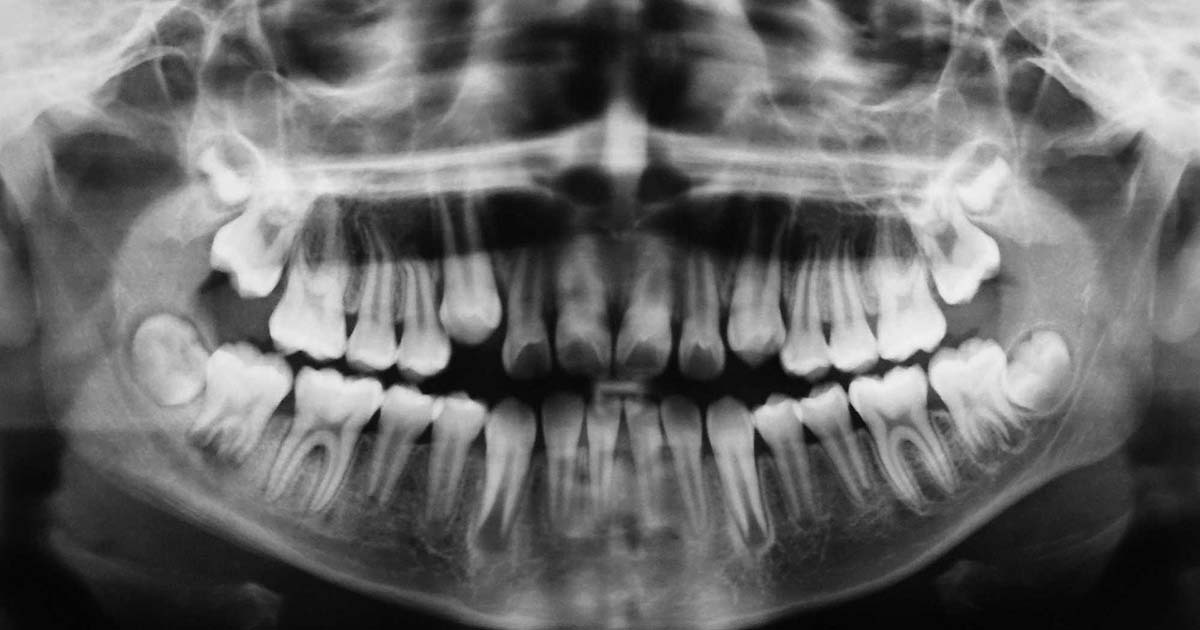

El origen del Alzhéimer podría estar relacionado con una enfermedad bucal

Diversos científicos han apuntado a una sorprendente hipótesis que refuerza la idea de que el origen del Alzheimer no solo es una enfermedad, sino una infección. Así lo defiende un nuevo estudio publicado en Science Advances en el que se vincula la enfermedad degenerativa con una infección bucal, según informa el diario El Confidencial.

El patógeno ‘Porphyromonas gingivalis’, que provoca la periodontitis crónica, ha sido descubierto en el cerebro de personas fallecidas por el Alzheimer, tal y como demuestra una investigación realizada por el microbiólogo de la Universidad de Louisville, Jan Potempa.

Hasta ahora, la periodontitis crónica y el Alzheimer se habían relacionado, aunque existían dudas de si era la periodontitis la que provocaba el Alzheimer o viceversa. En la actualidad, el haber encontrado gingipainas en personas que no fueron diagnosticadas de Alzheimer, da la posibilidad de que podrían haber desarrollado la enfermedad si hubieran vivido más años.

Los autores de la investigación defienden en su estudio que la “identificación de antígenos de gingipaina en los cerebros de personas con enfermedad de Alzheimer y también con patología de esta enfermedad pero sin haber sido diagnosticados de demencia, sostiene que la infección cerebral con Porphyromonas gingivalis no es el resultado de una atención dental deficiente después del inicio de la demencia o una consecuencia de la enfermedad, sino un evento temprano que puede explicar la patología encontrada en personas de mediana edad antes del deterioro cognitivo”.